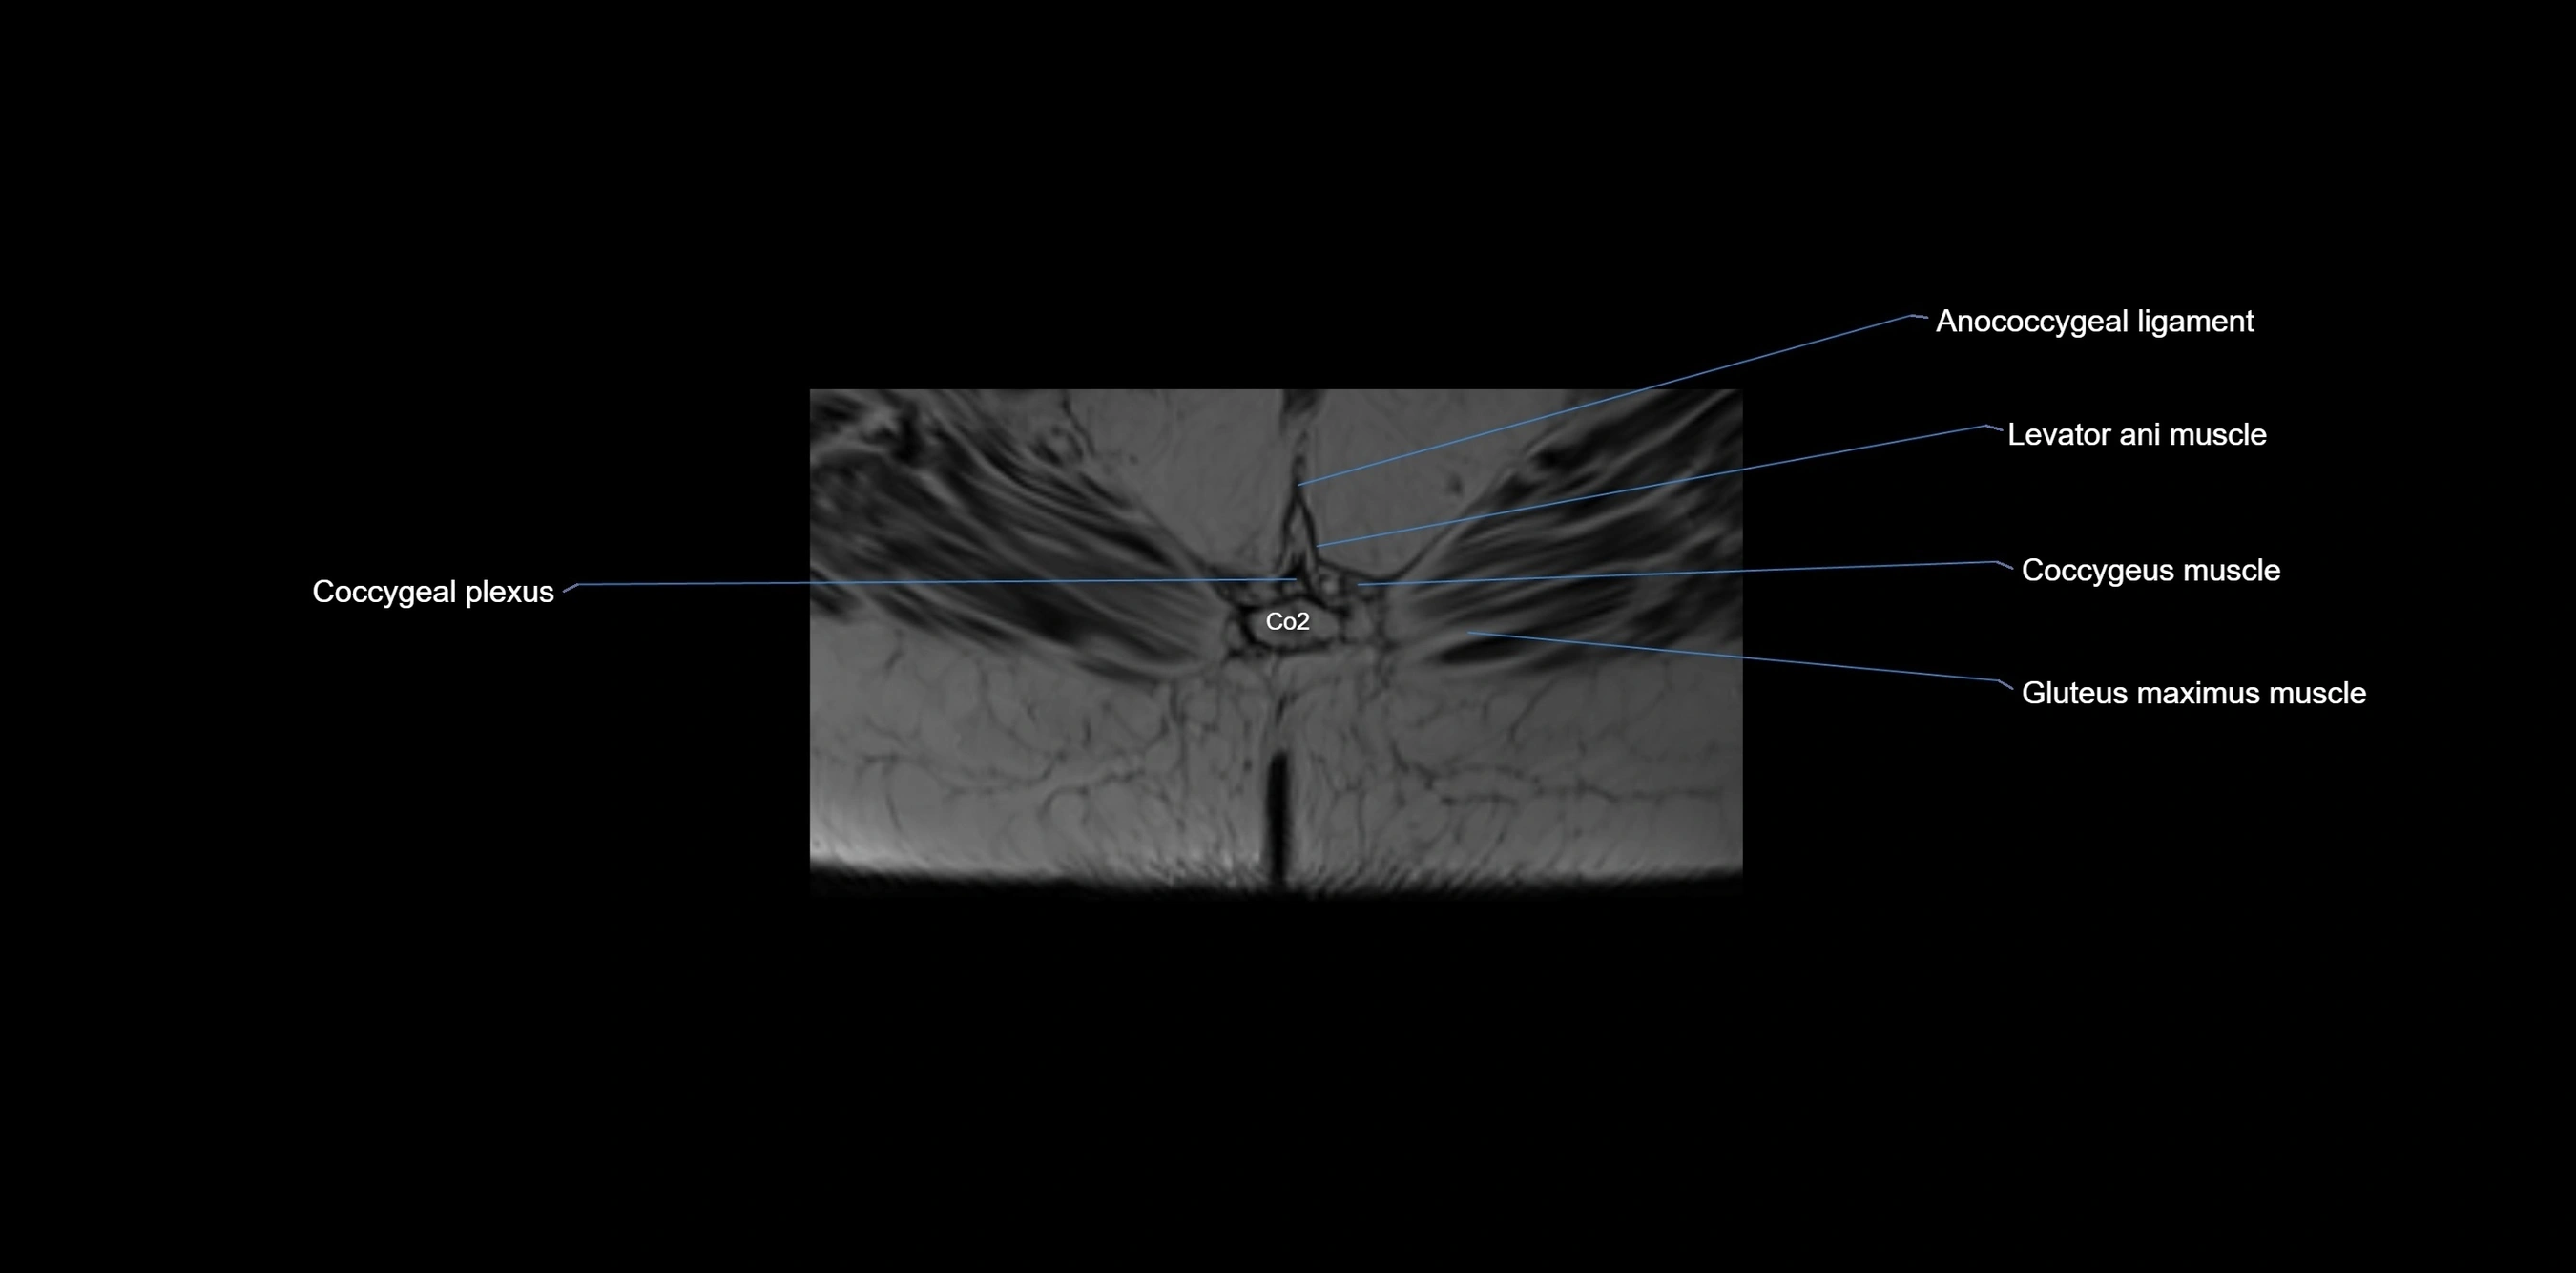

CT VRT image

image